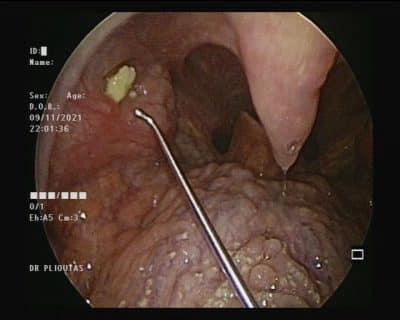

Οι αμυγδαλές έχουν γωνίες και σχισμές, όπου τα βακτήρια και άλλα υλικά, συμπεριλαμβανομένων των νεκρών κυττάρων και της βλέννας, μπορεί να παγιδευτούν. Όταν συμβαίνει αυτό, τα υπολείμματα αυτά μπορεί να συμπυκνωθούν σε μια λευκή ουσία που εγκλωβίζεται στην αμυγδαλή.

Οι πέτρες στις αμυγδαλές σχηματίζονται όταν αυτή η παγιδευμένη ουσία σκληραίνει ή ασβεστοποιείται. Αυτό τείνει να συμβαίνει πιο συχνά σε άτομα που έχουν χρόνια φλεγμονή στις αμυγδαλές τους ή επαναλαμβανόμενες κρίσεις αμυγδαλίτιδας.

Ενώ πολλοί άνθρωποι έχουν μικρές πέτρες στις αμυγδαλές τους, ορισμένοι -αν και είναι αρκετά σπάνιο- έχουν μεγαλύτερες πέτρες.